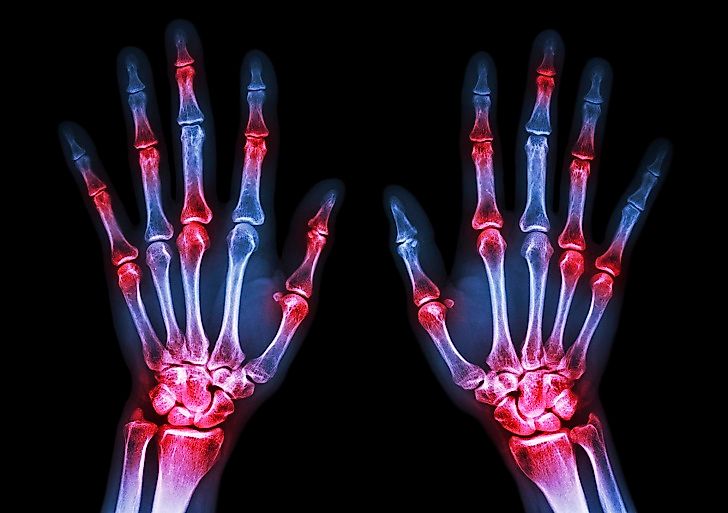

Arthritis in Hands Effective Tips for Treatment and Management Best State For Arthritis What are the five best states for arthritis? What about the best climates? Temperature, humidity, and barometric pressure changes can impact arthritis symptoms. Finding one of the best places to live with arthritis in the united states, which can make your life easier and may just ease your. Here’s a look at the best places to live if you have. Best State For Arthritis.